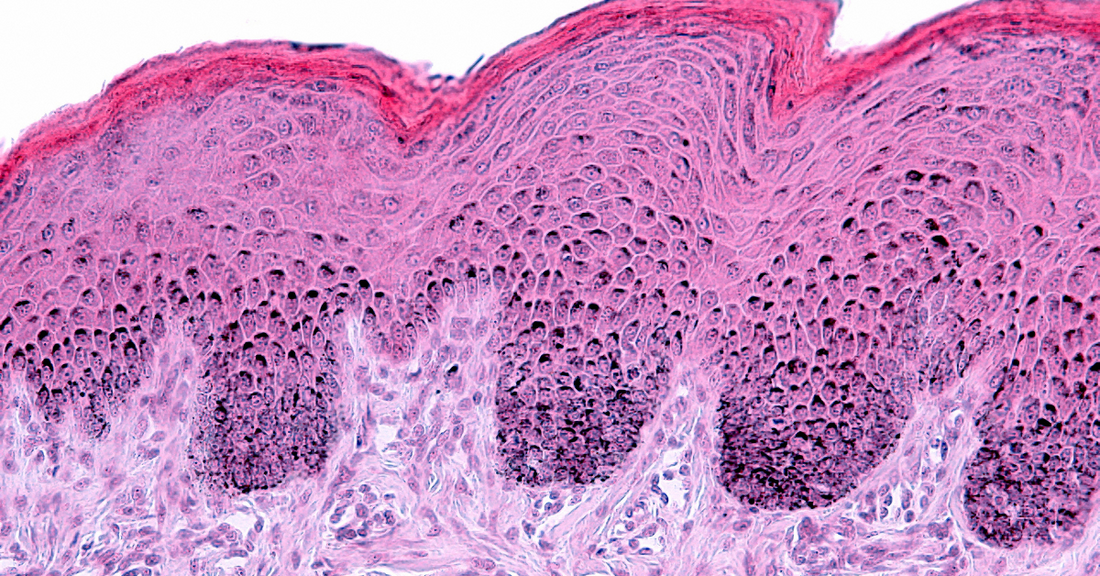

La peau comporte trois couches principales, chacune ayant un rôle bien précis :

1. L’épiderme : La couche superficielle qui constitue une barrière contre les agressions extérieures. Elle est constituée de cellules appelées kératinocytes, qui migrent progressivement vers la surface. C'est pour cela que notre peau s'exfolie naturellement.

2. Le derme : La couche intermédiaire, riche en collagène et en élastine, qui donne à la peau sa fermeté et son élasticité. C’est également là que se trouvent les vaisseaux sanguins, les glandes sébacées et les follicules pileux.

3. L’hypoderme : La couche la plus profonde, composée de tissus adipeux, qui protège contre les chocs et régule la température corporelle.

Chaque couche joue un rôle essentiel pour maintenir une peau saine et protégée. Ces trois couches forment une structure dynamique qui se régénère en continu.

Le renouvellement cellulaire correspond à la capacité de la peau à produire de nouvelles cellules et à éliminer les anciennes. Les nouvelles cellules sont produites dans la couche basale (la plus profonde de l’épiderme) et migrent vers la surface. Lorsqu’elles atteignent la couche cornée, elles meurent et forment une barrière protectrice avant de se détacher (desquamation ou exfoliation).